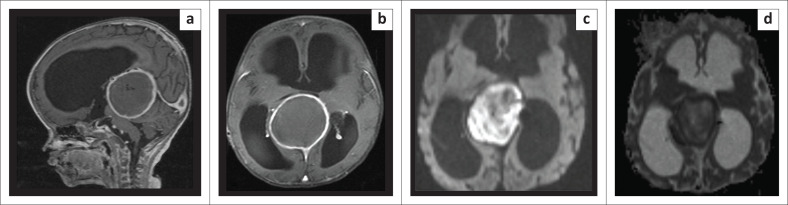

盖伦静脉动脉瘤畸形(VGAM)是一种罕见的先天性畸形,其特征是原始脉络膜动脉和正中前脑静脉(盖伦静脉的胚胎前体)之间的动静脉瘘。血管内技术改变了这些患者的治疗方法,改善了预后。一名八个月大的 VGAM 患者在使用乙烯-乙烯醇共聚物(EVOH)进行血管内栓塞治疗后,出现了罕见的并发症--化学脓肿。经保守治疗后,临床效果良好:贡献:EVOH栓塞术后的化学脓肿很少见,影像学鉴别包括脑脓肿和玛瑙肉芽肿。了解并成功识别这一实体至关重要,因为其治疗和预后各不相同。化学脓肿可采取保守治疗,预后良好。

Vein of Galen aneurysmal malformation (VGAM) is a rare congenital malformation characterised by arteriovenous fistulas between primitive choroidal arteries and the median prosencephalic vein, the embryonic precursor to the vein of Galen. Endovascular techniques have changed the management of these patients with improved prognosis. An eight-month-old with VGAM managed by endovascular embolisation using ethylene vinyl alcohol copolymer (EVOH) developed a chemical abscess - a rare complication. It was managed conservatively and showed promising clinical outcome.

Contribution: Chemical abscesses following EVOH embolisation are scarce - with imaging differentials, which include brain abscess and onyx granuloma. Knowledge and successful identification of this entity are essential as its management as prognoses differ. Chemical abscess is managed conservatively and has a good prognosis.